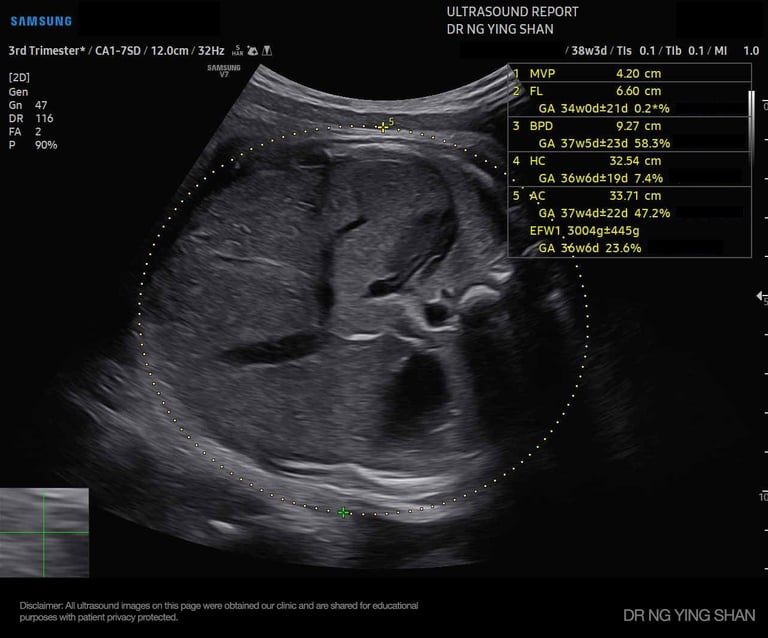

from 24

weeks onwards

Growth Scans

Monitors the baby’s size, fluid levels, and placenta health, especially if there are concerns about growth or complications.